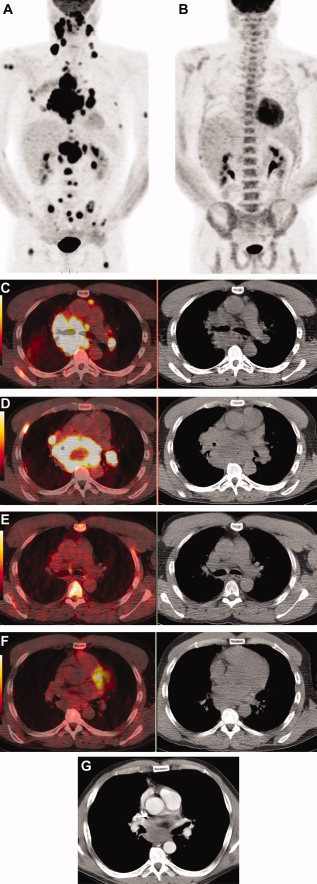

A 46-year-old male with diffuse large B cell lymphoma, stage IV was studied. Baseline maximum intensity projection (MIP) positron emission tomography (PET) image with [18F]fluorodeoxyglucose ([18F]FDG) (A) shows widespread disease, which is essentially resolved on interim scan after 4 cycles of chemotherapy (B). The interim scan also shows increased [18F]FDG uptake in bone marrow related to administration of granulocyte colony-stimulating factor (GCSF). (C,D) Transaxial CT and PET/CT fusion images at baseline show abnormal [18F]FDG uptake in extensive mediastinal and hilar lymphadenopathy as well as in bone lesions in a right rib and the right scapula. On interim scan (E,F) abnormal [18F]FDG uptake at all of these sites has resolved although residual enlarged lymph nodes remain. The sites are better seen on a contrast-enhanced CT (G) and measure up to 5.3 cm × 3.6 cm. Chemotherapy was continued for a total of 8 cycles. At the time of writing, the patient remained disease-free after 9 years of follow-up.

Subsequent to their acknowledgment of PET/CT as the most promising imaging modality for management of Lymphoma, the authors focused their review to on its role in this disease pathway. It being well understood that the clinical utility of [18F]FDG PET in lymphoma “depends on the intensity of radiotracer uptake in disease sites, which will affect the test accuracy for staging and characterizing residual masses after completion of therapy, as well as the role of the test in response assessment. The intensity of [18F]FDG uptake in lymphoma is determined by tumor histology, grade (eg, indolent versus aggressive NHL)”,181, 182 At the end of their extensive review the authors do mention that PET/MRI might become an important player in the management of this disease, especially in pediatric cases.